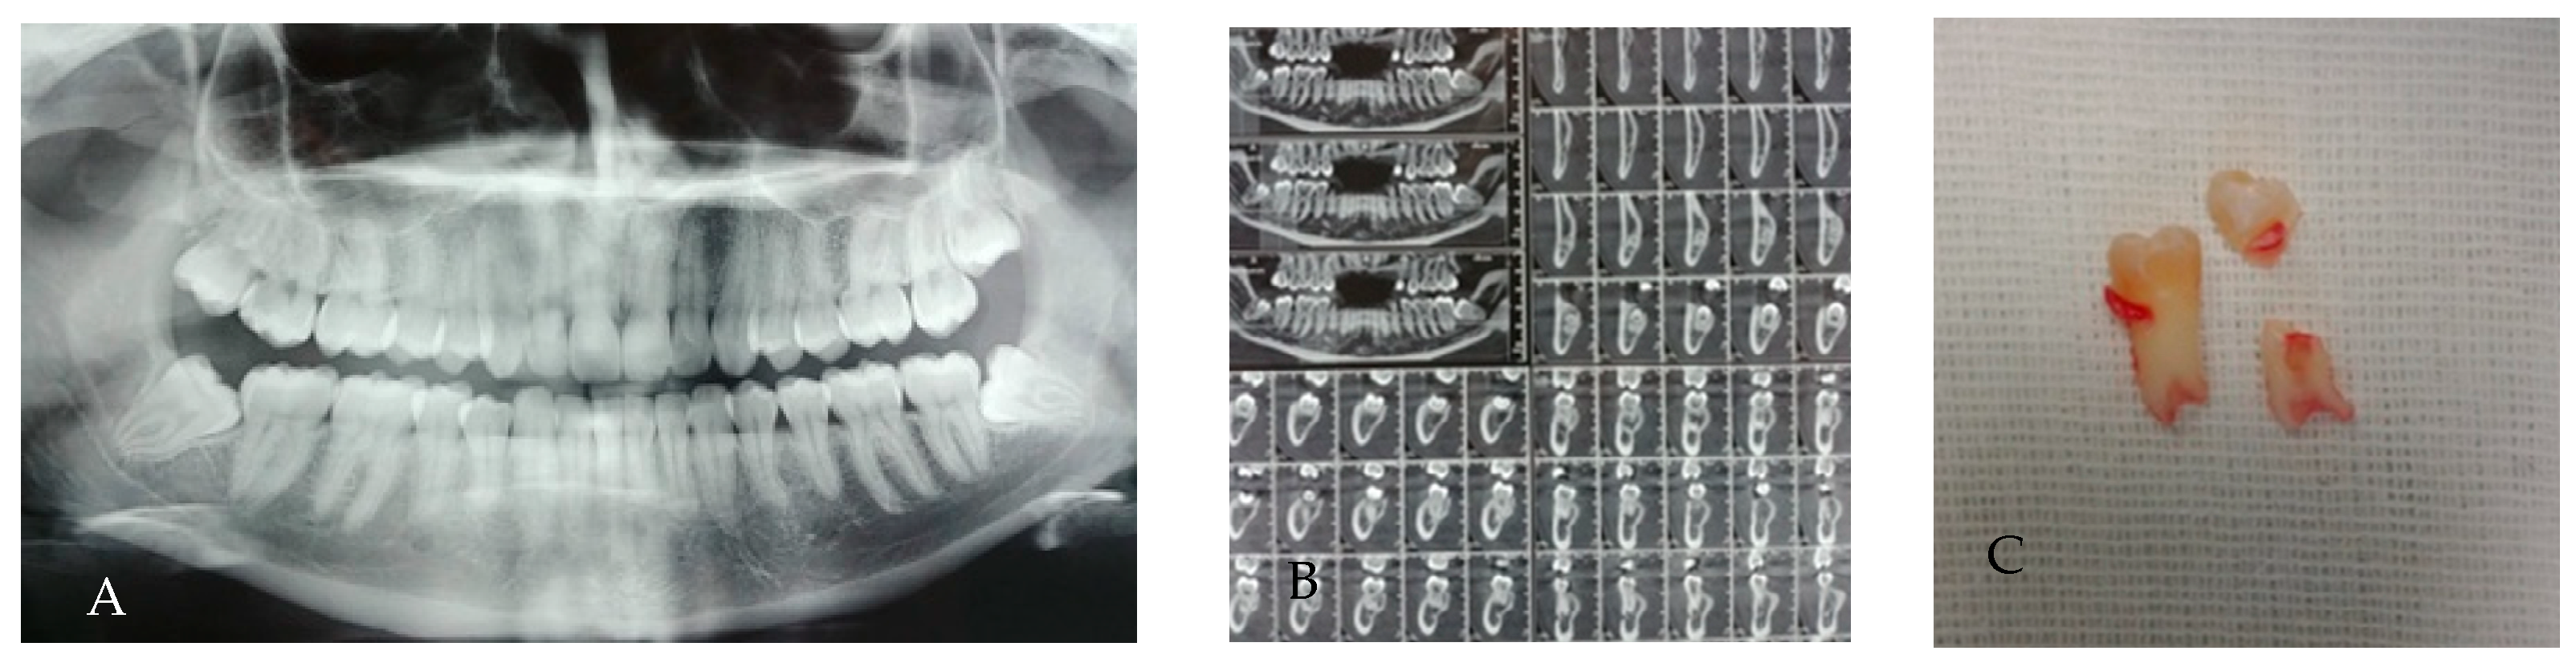

3.4. Taurodontism

- Hypotaurodont: mild displacement; furcation slightly apical, root length relatively preserved.

- Mesotaurodont: moderate displacement; larger pulp chamber, shorter roots.

- Hypertaurodont: severe displacement; very elongated pulp chamber, minimal root length, furcation close to the apex.

| Taurodontism | Li et al., 2023 [10]; Kırmızı et al., 2025 [11] | Chinese and Turkish-Cypriot | CBCT | Tooth-level prevalence 7–8%; MTM-specific rare |

| Hypo-/Meso-/Hypertaurodont | Apical displacement of pulp floor; root shortening | Tooth-level 7–8%; individual 20–29% (mostly non-MTMs) | Reduced elevator purchase; require wider coronal troughing; control sectioning | [10,11] |

| Taurodontism | 1–5% (MTM-specific) | Wider coronal troughing; careful elevators | [10,11] |